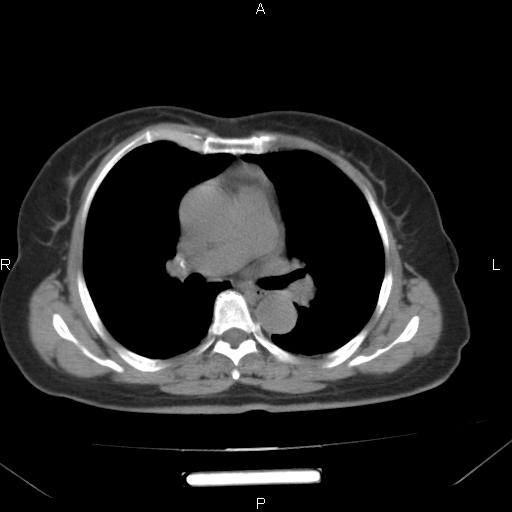

胸腺瘤

女、63Y 双眼睑下垂,早轻晚重。 胸腺瘤???

结果胸腺瘤